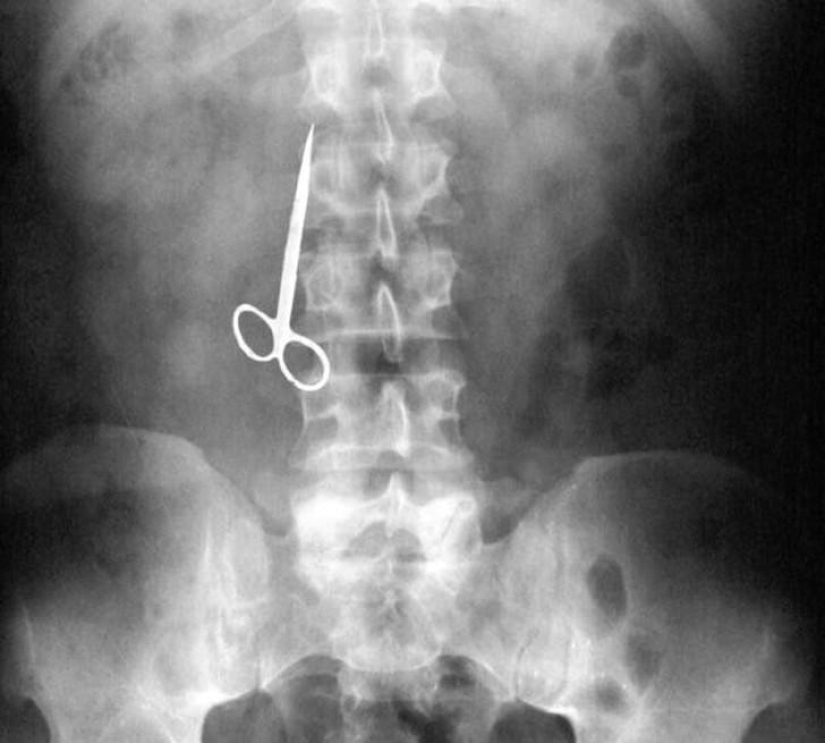

Scissors.